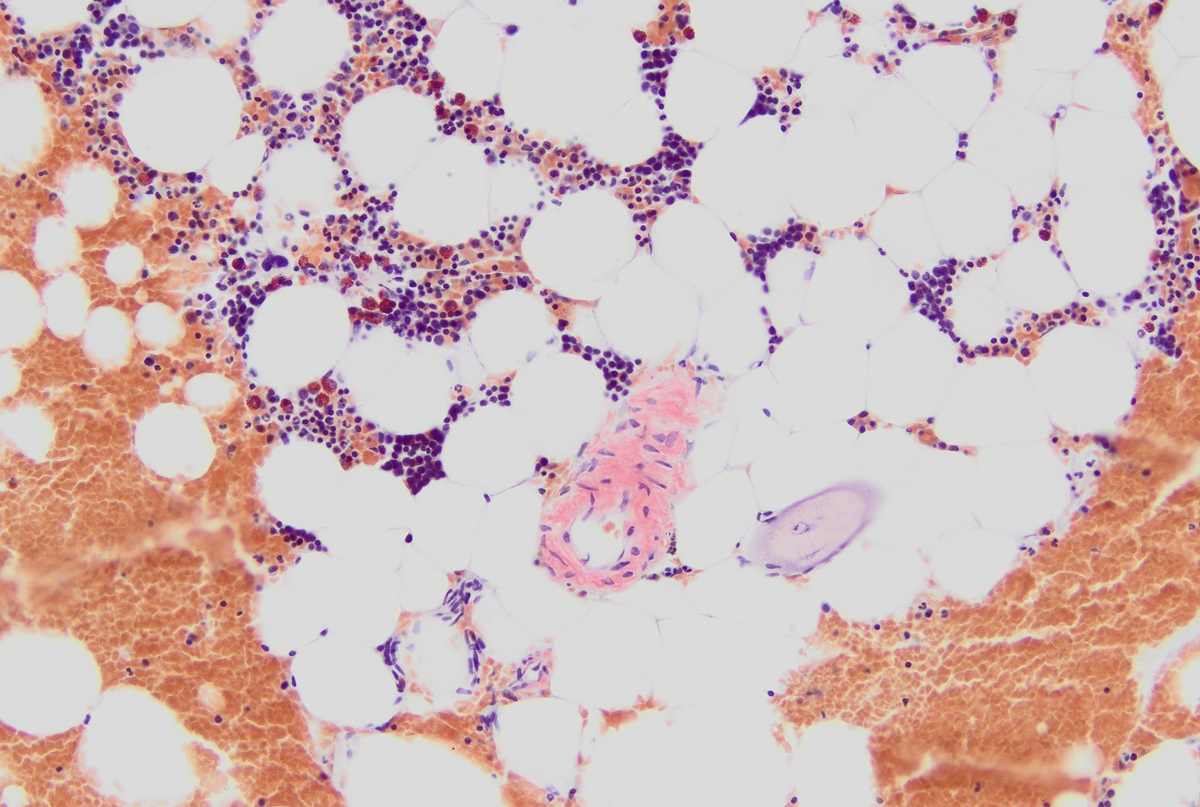

Microscopic (histologic) description

- Core biopsy (Am J Clin Path 1987;87:342):

- Interstitial clusters, nodules or sheets of plasma cells

- Areas of bone marrow may be spared with preserved hematopoiesis, other cases may have diffuse involvement and markedly suppressed hematopoiesis

- Prominent osteoclastic activity may be seen

- IHC to quantify plasma cells (CD138), stains for Ig kappa and lambda to establish clonality

Microscopic (histologic) images

Contributed by Genevieve M. Crane, M.D., Ph.D. and Tapan Bhavsar, M.D., Ph.D.